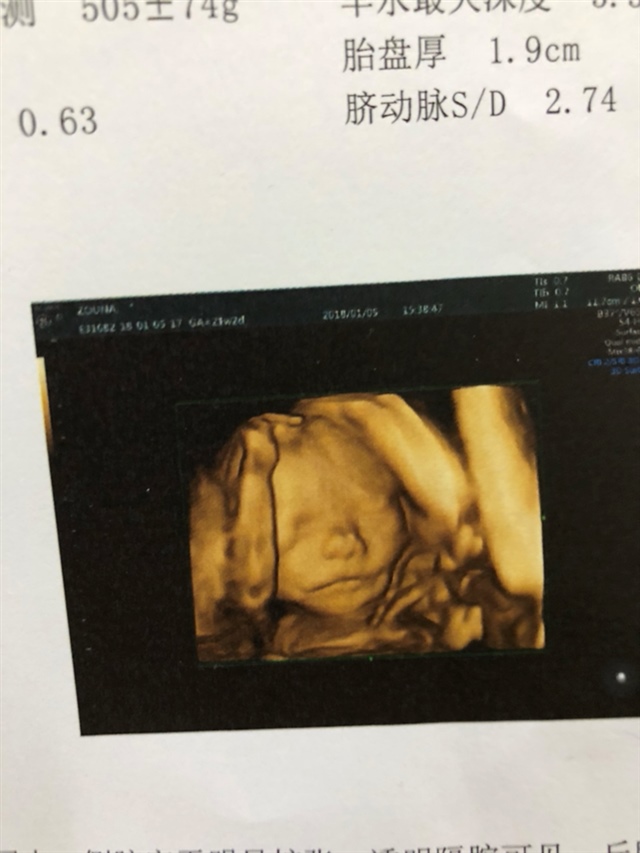

这是做的什么检查?

🕊鹿鹿🕊[帖主]:三维彩超